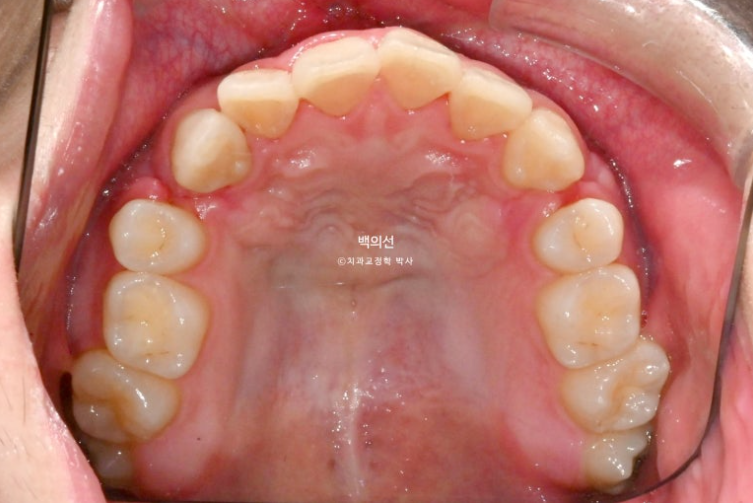

24년 10월, 돌출입 수술 한달 후 내원한 환자분 입니다.

24.10

돌출입 수술을 하면 수술 테크닉적으로 작은어금니가 있던 공간이 약 2mm 이상이 남게 됩니다.

송곳니 뒤쪽에 2mm 의 공간이 각각 남았습니다.

이렇게 애매하게 남은 공간을 앞니 배열을 위한 공간으로 사용하는 것이 돌출입 수술교정의 핵심입니다.